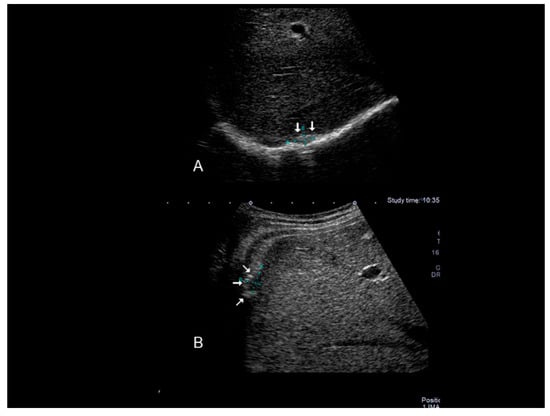

Figure 2. Ultrasonographic images of one nodule (AC) (see thin with arrows), of scar endometriosis infiltrating the external oblique muscle in a woman with a previous cesarean section some years before cesarean scar endometriosis.

Scar endometriosis may present as a hypoechoic solid nodule with hyperechoic spots or strands which represent fibrosis within the scar tissue, a hyperechoic peripheral ring, spiculated borders and a single vessel entering the nodule from the periphery (Figure 1 and Figure 2) [11,12,13]. In nodules larger than 30 mm, cystic portions and/or fistulous tract, loss of oval or round shape, multiple vascular pedicles, and central vascularization are more frequent [12].